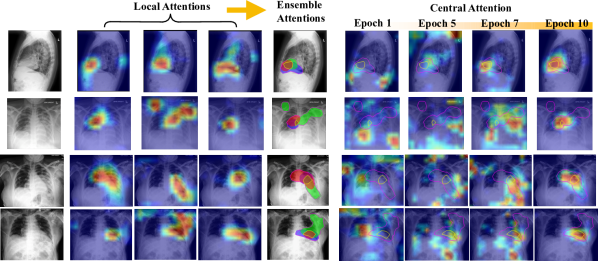

Refer to caption

Figure 3: Illustration of how ensemble attention can effectively guide the central model to focus on the correct region. In ensemble attention visualization, we threshold the activation at 0.5 and color the activated area red, green, and blue for the three locals, respectively. We contour the boundary of attention consensus/diversity region with yellow/black.